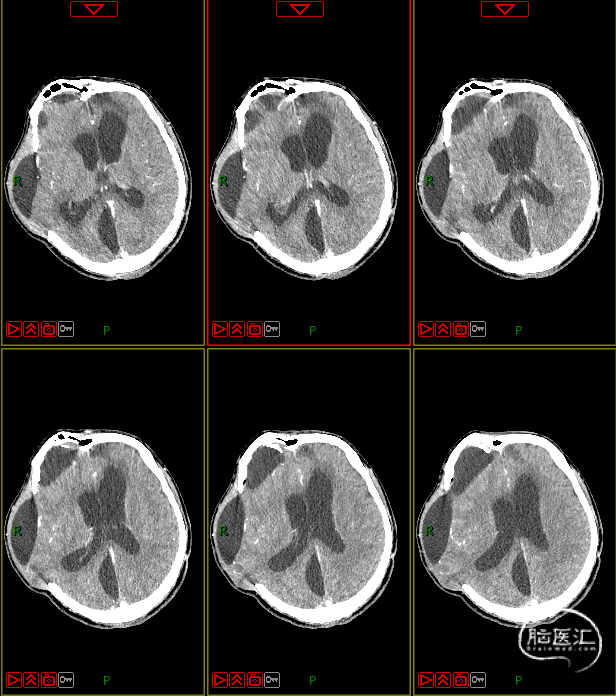

病史及症状描述:主诉:重型颅脑外伤术后意识障碍50天(7月30日入院);现病史:患者2023年6月11日因高处坠落伤在外地行开颅手术等治疗,病情平稳后带气管套管转回湘潭市中心医院(后续简称“我院”)治疗。

入院查体:GCS=E2VTM2=4T分,右侧瞳孔直径约4mm,对光反射迟钝,左侧瞳孔约3mm,对光放射灵敏,四肢关节被动屈伸活动无受限,四肢肌张力偏高,肌力查体无法配合,病理征未引出。

入院诊断:1. 右侧额颞部硬膜下血肿清除术后;2. 颅骨后天性缺损;3. 脑内多发软化灶形成;4. 脑积水;5. 左额骨凹陷性骨折;6. 颅底骨折;7. 左股骨干骨折内固定术后;8. 坠积性肺炎、胸腔积液;9. 气管切开术后;10. 右眼挫伤;11. 下肢肌间静脉血栓;12. 低蛋白血症。

4. 动态复查头部CT

8月21日复查CT:硬膜下积液增加,脑室扩张明显,间质性水肿加重;对患者治疗方案进行调整,转神经外科治疗。